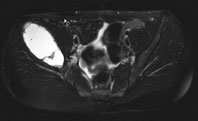

Die Röntgenuntersuchung von Becken/Hüfte zeigt eine septierte geographische Osteolyse in der Ala und im Korpus des Os Iliums rechts. Das Röntgenbild und die Aufnahmen der nachfolgenden MRI-Untersuchung sehen Sie hier:

T2 FS, axial, 5 mm

Bild vergrössern